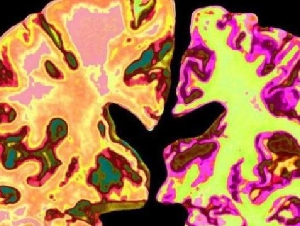

阿兹海默症可逆转 哈佛团队已着手人体临床试验

英国《自然》(Nature)期刊报道指出,美国哈佛大学的科学家在阿兹海默症研究上取得突破,发现一种可能逆转记忆丧失的药物,并指出其关键与“锂元素缺乏”有关。 研究团队发现,大…